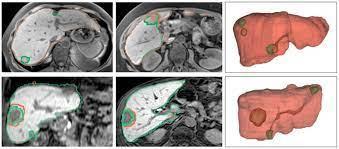

Module 1 - Image Segmentation

Module 5 - Image Segmentation using CNNs

Full Scale Medical Image Analysis